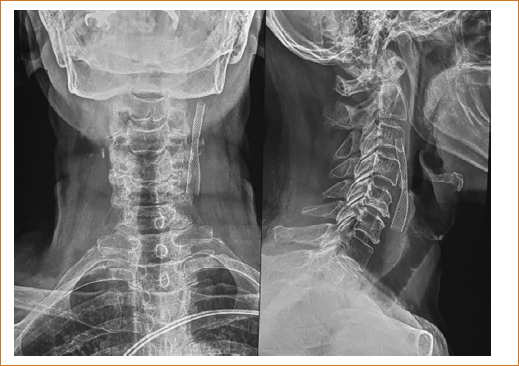

La paciente continuó con manejo médico con restricción hídrica, insulina de acción rápida por requerimientos, furosemida 10 mg/12 h, apixabán 2.5 mg/12 h, atorvastatina 40 mg/24 h y esomeprazol 40 mg/24 h por vía intravenosa. No presentó deterioro de la función renal y en las siguientes 72 horas la nueva depuración de creatinina se reportó en 42 ml/min. Metabólica y hemodinámicamente continuó compensada y neurológicamente consciente, orientada, Glasgow 15 puntos, sin déficit motor focal, movilizando sus cuatro extremidades con fuerza muscular normal, reflejos de estiramiento muscular normales acorde a su edad, no disártrica, no disfágica, sin ataxia, íntegra de juicio y raciocinio, marcha normal, tolerando la vía oral y sin compromiso en sitios de arteriopunción. La paciente egresó por mejoría 5 días después del cateterismo, con tratamiento multidisciplinario y seguimiento en la consulta externa de medicina interna. Desde entonces hasta septiembre de 2025 presenta mejoría de su clase funcional cardiaca, estabilidad metabólica con HbA1c < 7.4% y estabilidad hemodinámica con presión arterial promedio 146/84 mmHg. El ultrasonido Doppler carotídeo de control tardío del 11 de septiembre 2025 mostró stent carotídeo estable, con adecuado flujo sanguíneo (Figs. 3 y 4). Las radiografías simples de cuello permitieron identificar fácilmente el stent, su ubicación y la ligera estenosis residual (Fig. 5).

Figura 5. Radiografías anteroposterior y lateral de cuello.